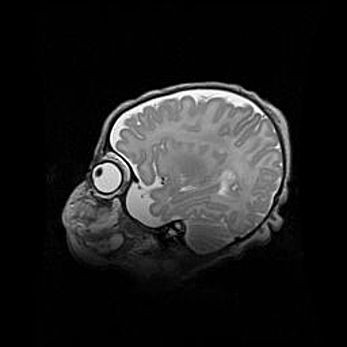

Множественные кисты обоих полушарий головного мозга, наибольшая из них в правой затылочной области. Ассиметричная атрофическая гидроцефалия.

Возраст: 7 месяцев

Вес: 5660 г

Пол: мужской

Окружность головы: 41,5 см

Срок гестации: 28-29 недель

Кисты головного мозга развиваются в результате многоочаговых некрозов вещества мозга и возникают вследствие перенесенной перинатальной инфекции, менингитов, энцефалитов, асфиксии, родовой травмы, расстройств мозгового кровообращения различного генеза. Образованию кист в веществе головного мозга плодов и новорожденных способствуют такие факторы, как высокое содержание в нем воды, недостаточная (или отсутствие) миелинизация и слабая астроглиальная реакция на повреждение.

Кисты могут сочетаться с гидроцефалией и другими поражениями головного мозга.